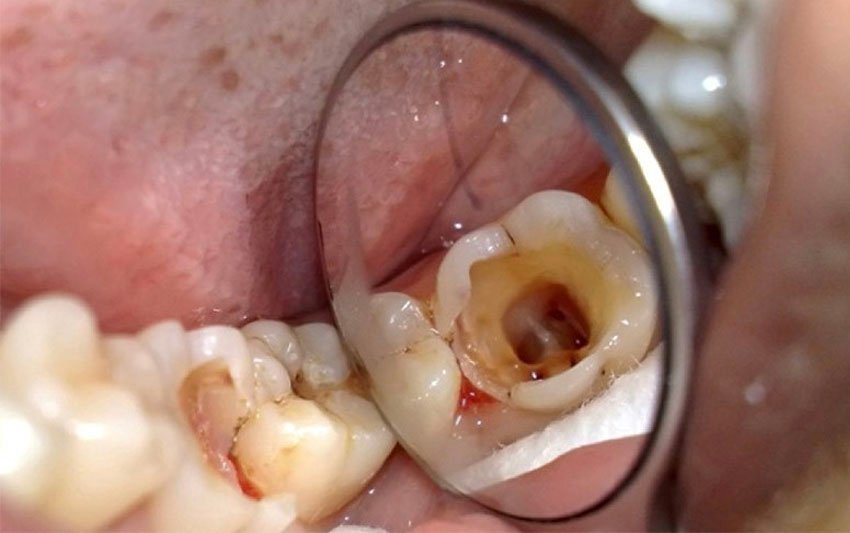

Trám răng sâu

Dịch vụ trám răng tại Nha Khoa 3C sử dụng vật liệu composite cao cấp, có màu sắc tương đồng với răng thật, mang lại hiệu quả thẩm mỹ tự nhiên cùng độ bền lâu dài. Kỹ thuật trám chính xác giúp bịt kín lỗ sâu, ngăn ngừa vi khuẩn xâm nhập trở lại và giảm thiểu cảm giác ê buốt sau điều trị.